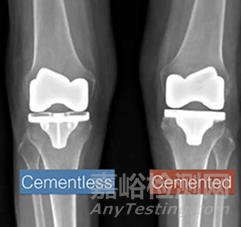

無骨水泥膝關(guān)節(jié)假體技術(shù)臨床應(yīng)用激增

據(jù)美國 AAOS 注冊數(shù)據(jù)顯示,無骨水泥固定的 TKA 應(yīng)用比例從 2012 年的 2% 激增至 2023 年的 22%。這背后,是年輕患者群體增加、臨床對長期穩(wěn)定性的要求、以及手術(shù)流程向快節(jié)奏轉(zhuǎn)型的多重驅(qū)動因素——材料與結(jié)構(gòu)創(chuàng)新正在重塑普外科格局。